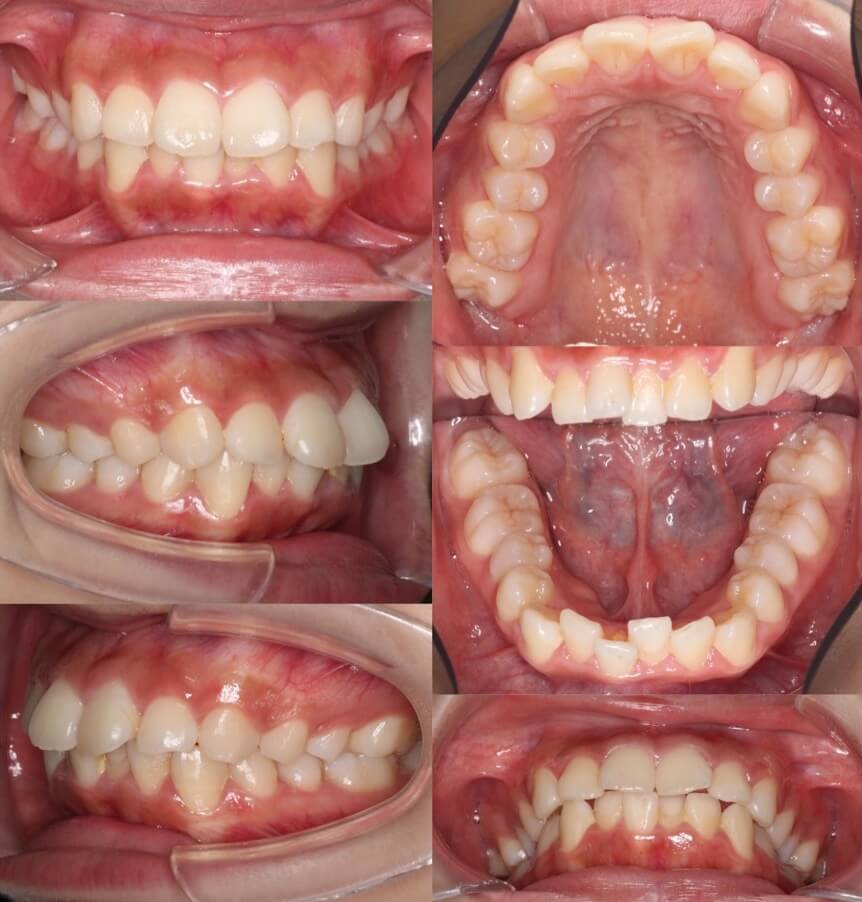

「男性は顔が引き締まる」

高校生男性・唇側矯正装置・下あご後退型

当初は、抜歯矯正治療にするかしないかで、治療方針に迷ったケースですが、最終的には患者さんの希望に沿って抜歯矯正治療にしました。歯の動きがゆっくりであったため、治療期間が3年を超えてしまいました。

<症例概要> 難易度:★★★★☆

主訴:口元の突出・前歯のガタツキ

年齢・性別:高校生男性

住まい:千葉県八千代市市

症状:下顎後退・叢生

治療方針:抜歯空隙の閉鎖(最大固定)

治療装置:唇側矯正装置

固定:歯科矯正用アンカースクリュー(頬側x2)

抜歯:上下第一小臼歯(計4本)

治療期間:3年4か月

リテーナー:上下プレートタイプ+フィックスタイプ

治療費用:968,000(税込)

代表的副作用:痛み・治療後の後戻り・歯根吸収・歯髄壊死・歯肉退縮